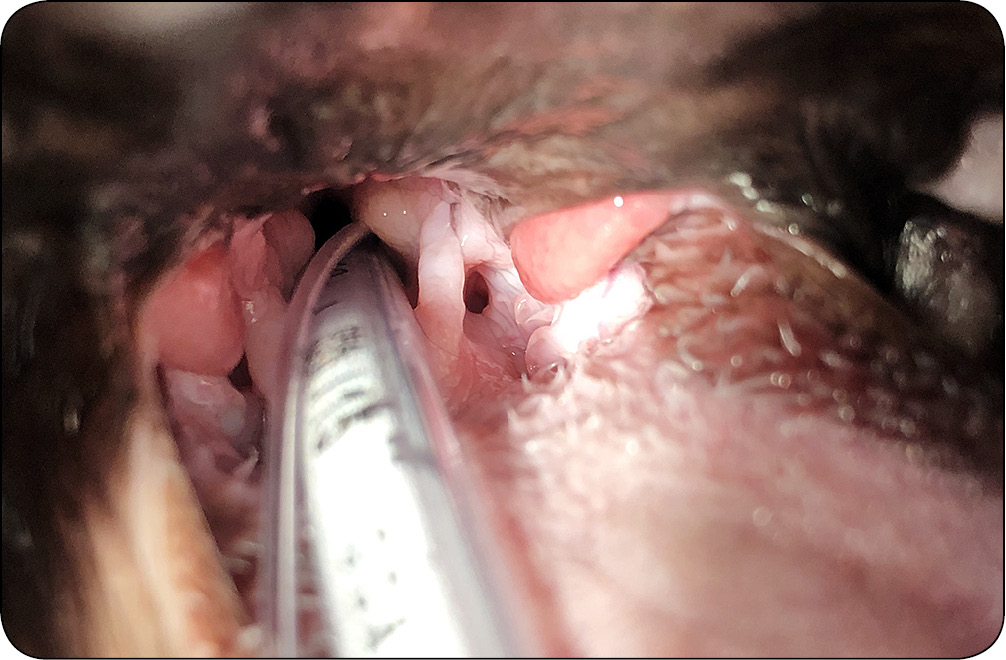

W niektórych sytuacjach szwy mogą ulec zerwaniu lub rozluźnieniu, co może wymagać ponownej interwencji chirurgicznej. Szczególnie u psów brachycefalicznych, które mają pogrubiały język, a także u kotów, których język posiada wyrostki. Ciągła manipulacja językiem może prowadzić do rozwiązania i zerwania szwów. Warto zatem rozważyć zaopatrywanie rany za pomocą pojedynczych szwów.

Dość często przy braku zachowania należytej ostrożności i nieumiejętności specjalisty chirurga może wystąpić krwawienie z obszaru operowanego. Naczynia podniebienne [...]